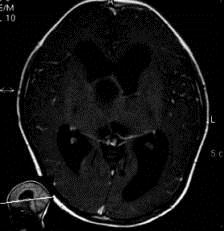

问题 病历摘要:??患者女性,6岁,半年来感觉视力模糊,近10天出现反复头痛,间有恶心呕吐,精神转差,查体:神志清楚,身高90cm,体重25Kg,血压90/55mmHg,右眼视力4.6,左眼视力4.8,双侧视乳头水肿,颈软,伸舌居中,四肢肌张力正常,肌力5级,双侧Babinski征(-)。 入院检查头部MRI,如图所示,诊断有可能是?

选项 A.垂体腺瘤 B.生殖细胞瘤 C.颅咽管瘤 D.视神经胶质瘤 E.蛛网膜囊肿 F.鞍结节脑膜瘤 G.脑积水

答案 CG